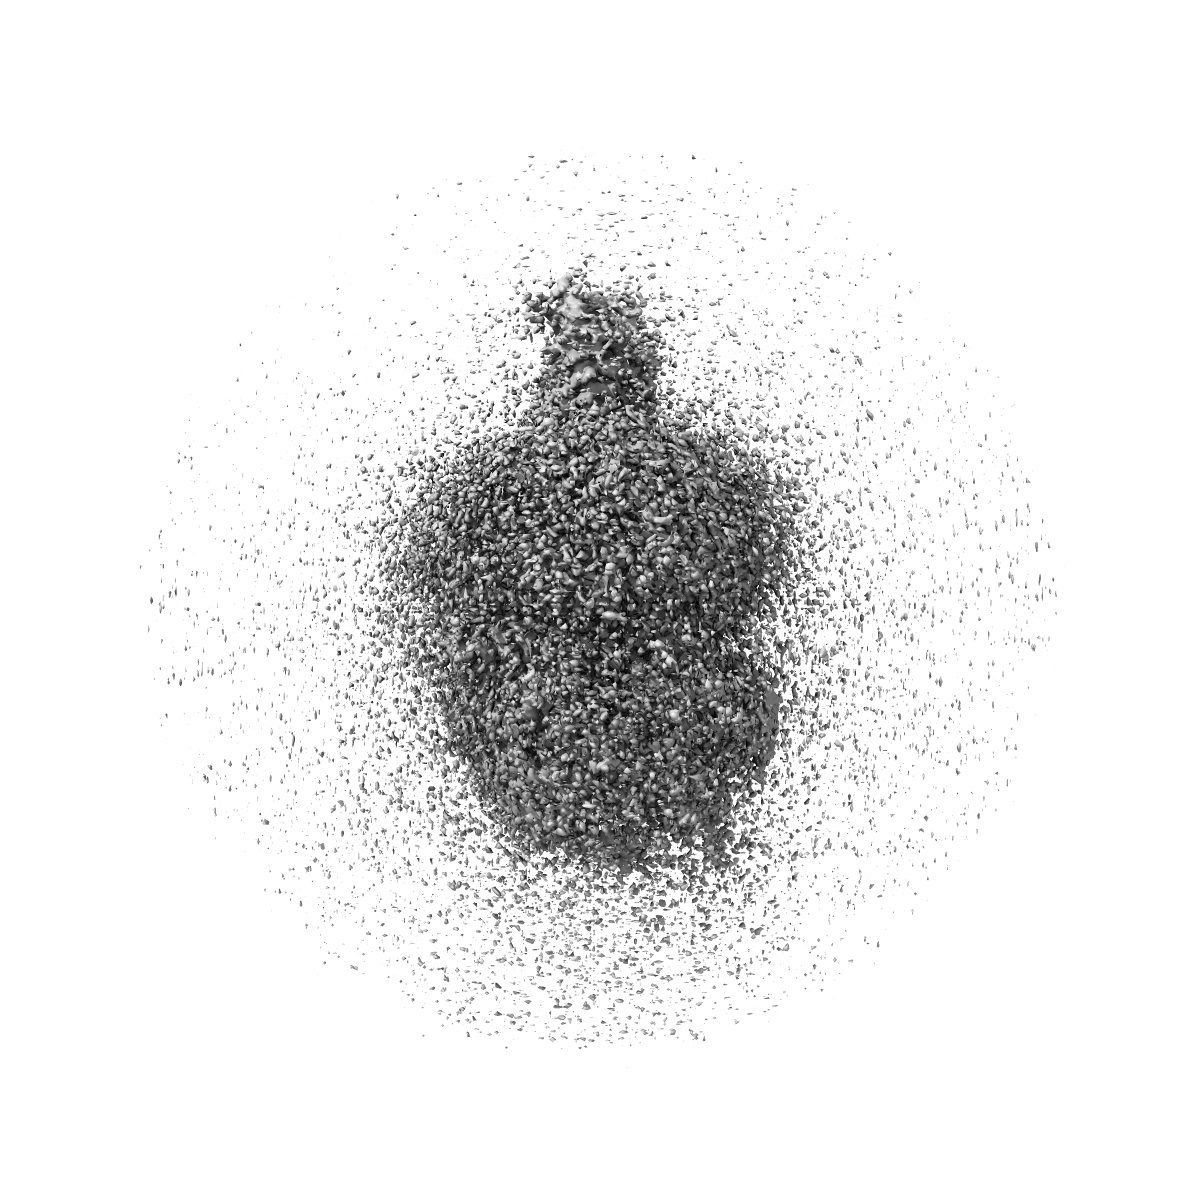

Cryo-EM structure of the retatrutide-bound human GCGR-Gs complex

Single-particle2.84 Å

Sample: Cryo-EM structure of the retatrutide-bound human GCGR-Gs complex